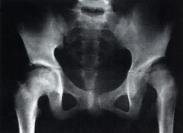

單純性髖關節前脫位(圖1),遠遠少見于后脫位,據布拉(Brav)統計為后脫位的14%,阿福克(Aufanc)等統計為后脫位的4%,沙摩波遜(Thompson)等統計為后脫位的9%。